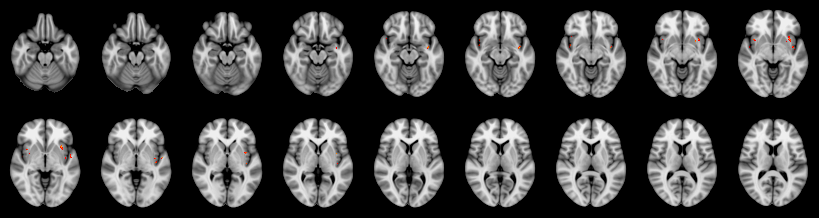

Pain study, Voxel-level, Corrected

Combined

Friston:

IUT/Conjunction/Nichols:

Hotelling T2: